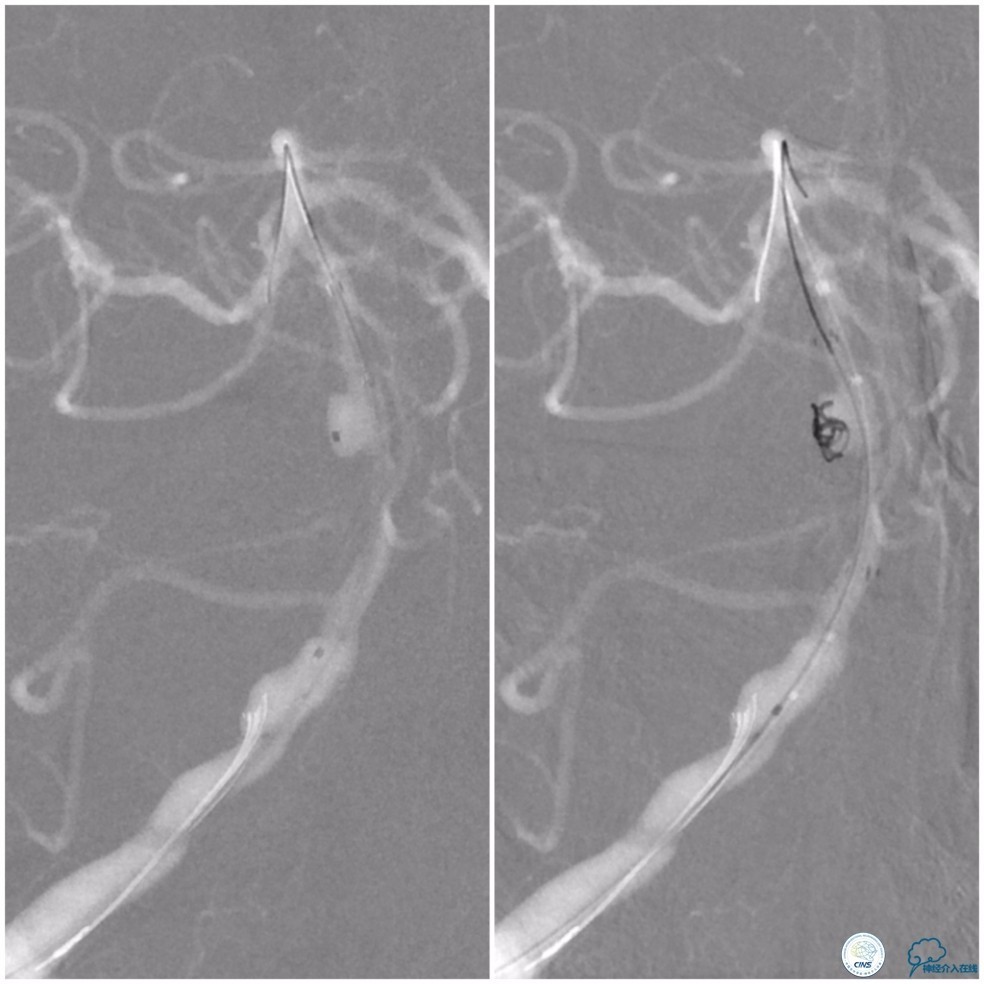

动脉粥样硬化狭窄合并动脉瘤的处理,因治疗狭窄和栓塞动脉瘤的两套系统常需要并列使用,事先要考虑所用导引导管是否能完全容纳两套系统,如本例8F导引导管到位困难,故只能改用两套系统完成治疗(图14)。

图14

此外对于邻近动脉瘤的狭窄扩张时,可以考虑使用长度稍长一点的球囊,尽量覆盖动脉瘤颈,避免扩张过程中球囊损伤动脉瘤。